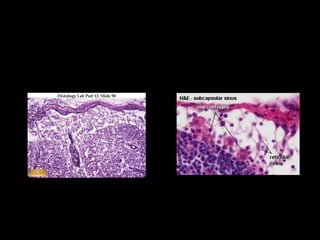

Okružen je fibroznom kapsulom koju probija

veliki broj tzv. aferentnih limfnih sudova koji

donose limfu koja se izliva u subkapsularni ili

marginalni sinus.

Ispod subkapsularnog sinusa se nalazi KORA:

spoljašnji korteks i unutrašnji parakorteks.

U spoljašnjem korteksu su smešteni gustiU spoljašnjem korteksu su smešteni gusti

agregati limfocita koji čine folikuli. U srediniagregati limfocita koji čine folikuli. U sredini

folikula se nalazi svetlija zona koja se nazivafolikula se nalazi svetlija zona koja se naziva

germinativni centar- a oko njega je tamnijagerminativni centar- a oko njega je tamnija

zona-korona. Deo okrenut izvoru infekcijezona-korona. Deo okrenut izvoru infekcije

naziva se kapa i sadrži B memorijske limfocite.naziva se kapa i sadrži B memorijske limfocite.

Ovakav folikul se naziva sekundarni folikuli.Ovakav folikul se naziva sekundarni folikuli.

Folikuli bez germinativnog centra se nazivajuFolikuli bez germinativnog centra se nazivaju

primarni folikuli.primarni folikuli.